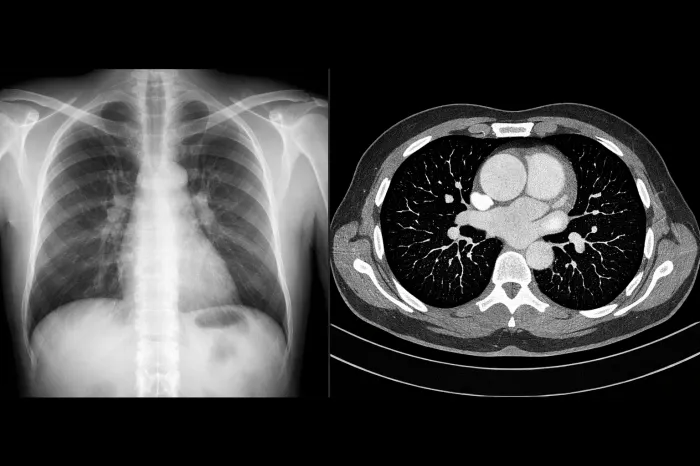

폐결절이란 폐 조직 안에 생긴 작은 덩어리를 의미합니다. 보통 흉부 엑스레이나 CT 검사에서 우연히 발견되는 경우가 많으며, 크기는 대개 3cm 이하입니다. 이보다 큰 경우에는 다른 용어로 구분하기도 합니다. 폐결절은 하나만 보일 수도 있고, 여러 개가 동시에 발견되기도 합니다.

폐결절이 발견되면 일정 간격으로 CT 검사를 통해 크기와 형태 변화를 확인합니다. 보통 3개월, 6개월, 1년 단위로 추적 관찰을 하게 되며, 변화가 없다면 검사 간격이 점점 늘어납니다.